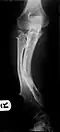

-

Multiple osteochondromas causing deformity of the forearm (shortening of the radius with secondary bowing of the ulna) -